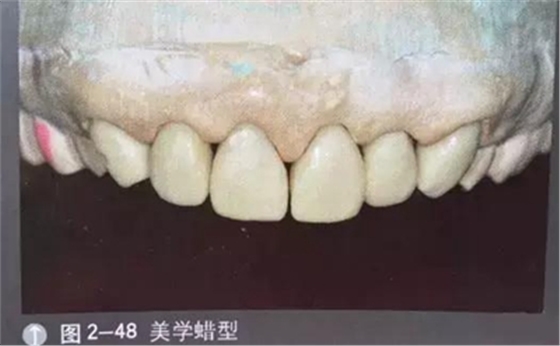

診斷蠟型